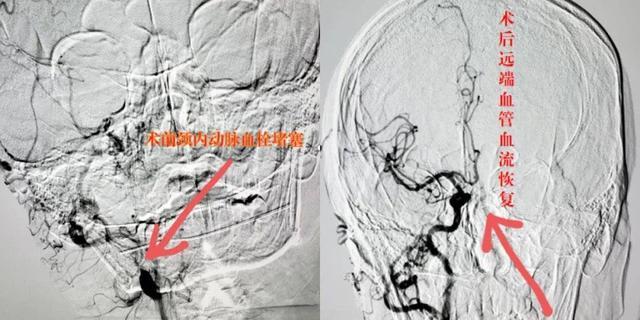

彭州市首例颈内动脉取栓让他转危为安